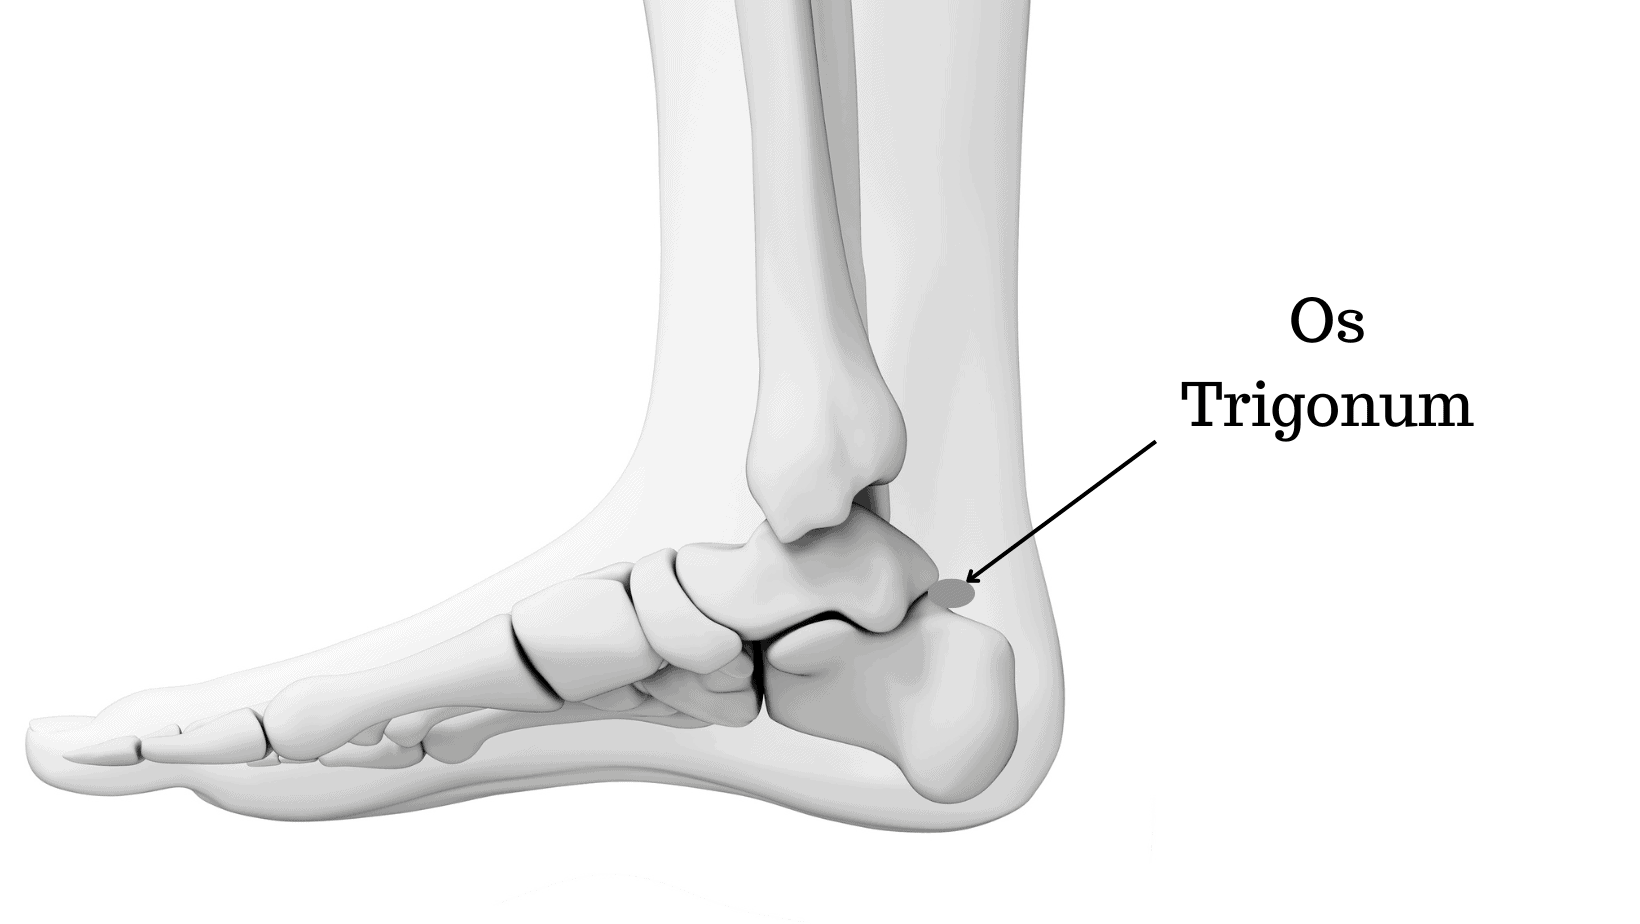

Os trigonum — это анатомический вариант развития стопы/аномалия развития, представляющая собой отдельную костную структуру, расположенную кзади от таранной кости.

Формируется из не слившегося вторичного центра окостенения таранной кости